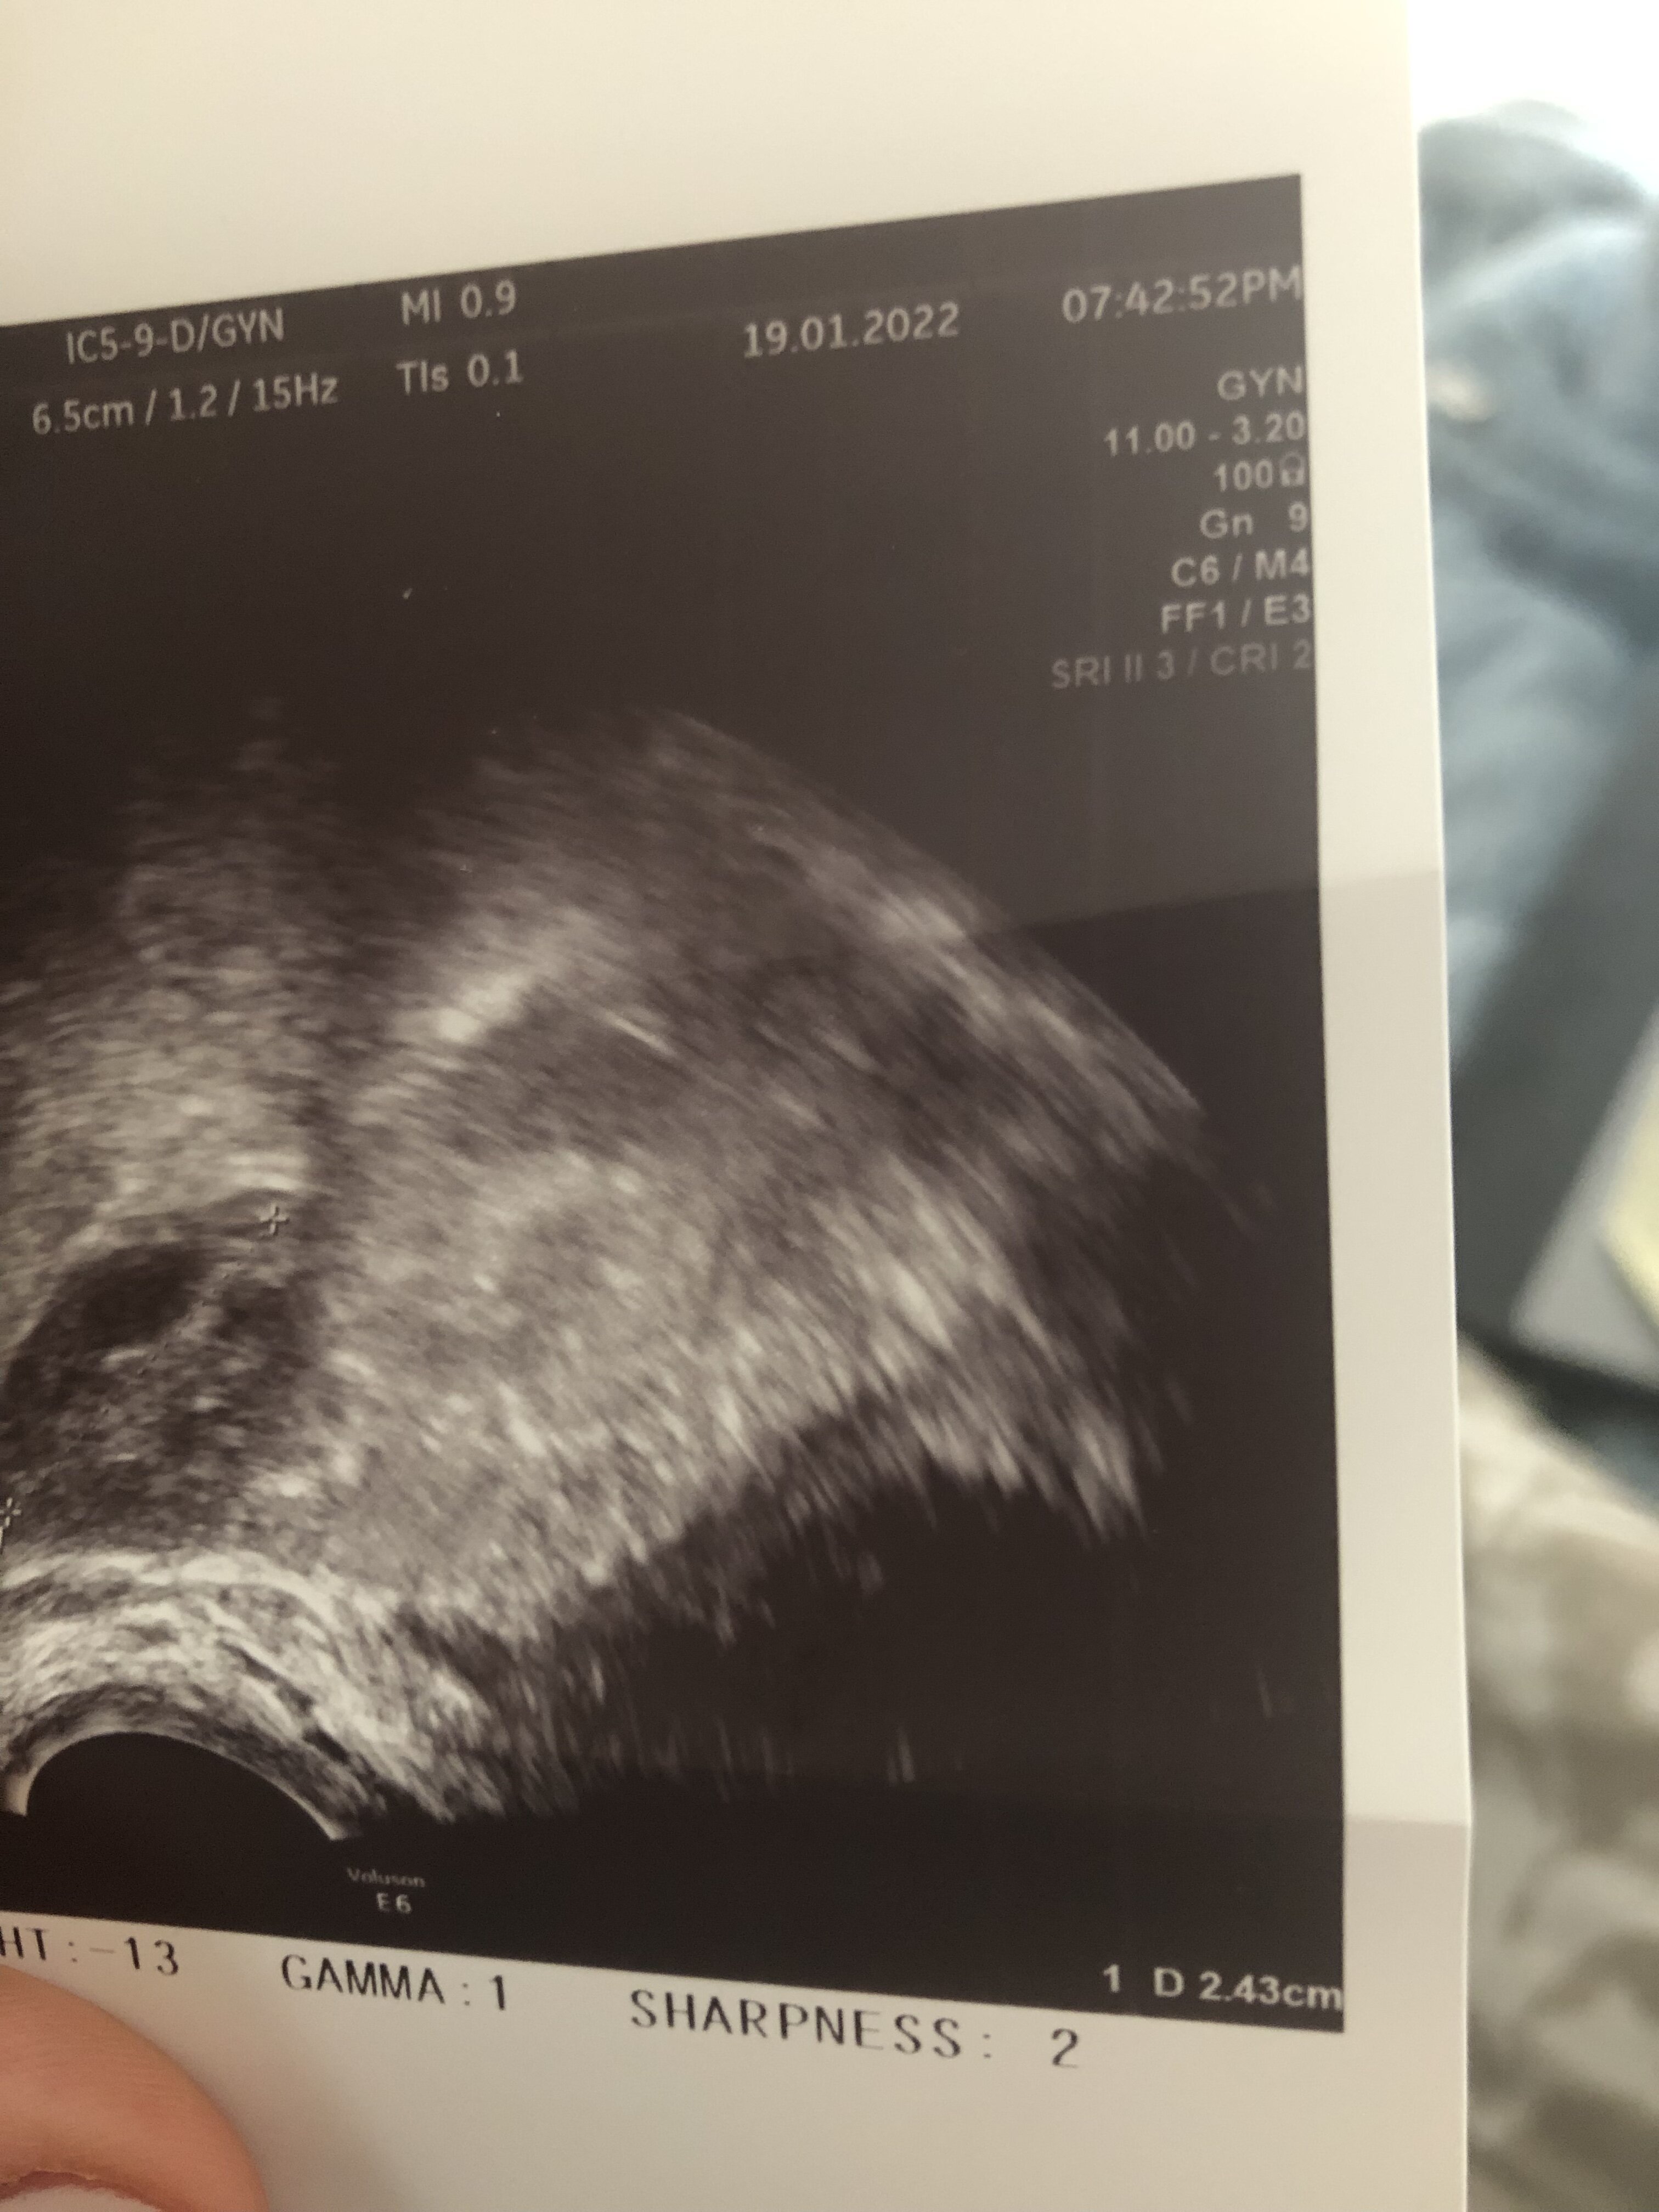

W którym miejscu na zdjęciu będzie to endometrium? To będzie to ze zdjęcia 0,75? Takie miałam w 14dc w 15 owu a w 16 0,92 jeśli dobrze odczytuje.A co masz na opisie? Powinnaś mieć grubość endometrium, wielkość jajników i wielkość pęcherzyków dominujących przynajmniej w 2 wymiarach.

A pokaż całość zdjęcia z tym wymiarem 0,75 bo ucięłaś połowę. To może być oczywiście endometrium.W którym miejscu na zdjęciu będzie to endometrium? To będzie to ze zdjęcia 0,75? Takie miałam w 14dc w 15 owu a w 16 0,92 jeśli dobrze odczytuje.

Wrzucam akurat z dnia po owu 0,92 jest o ile coś widaćA pokaż całość zdjęcia z tym wymiarem 0,75 bo ucięłaś połowę. To może być oczywiście endometrium.

Szczerze Ci powiem pierwszy raz widzę taki obraz endometrium, więc nie mam bladego pojęcia czy to to. Ale z drugiej strony nie jest to ani jajnik ani nic innego. Szkoda że nie dostałaś opisuWrzucam akurat z dnia po owu 0,92 jest o ile coś widać![]()